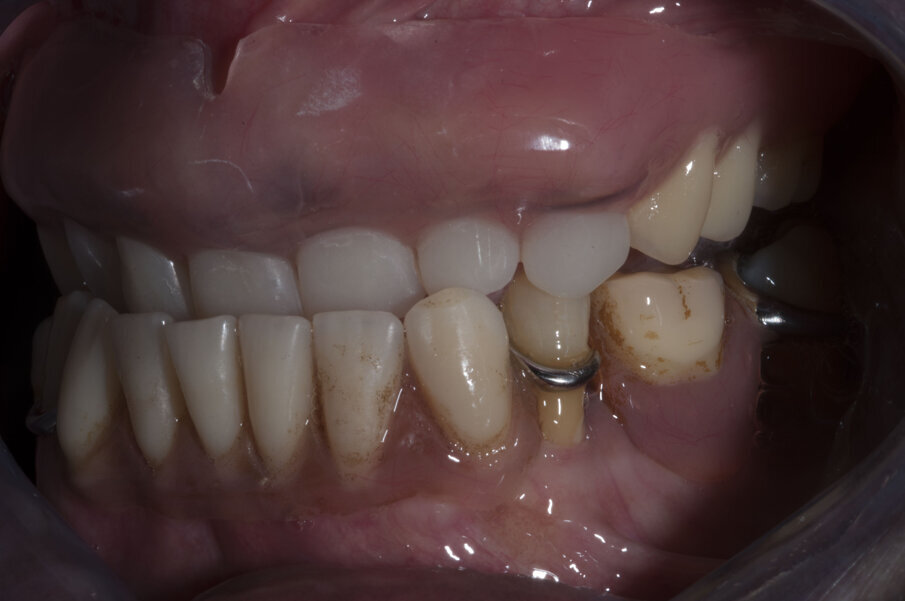

Nel frattempo il laboratorio, avendo l’impronta fin dal giorno della chirurgia, ha provveduto a fabbricare il modello maestro sul quale preparare un primo provvisorio avvitato da inserire sessanta giorni dopo la chirurgia (Figg. 29-32). La struttura definitiva viene disegnata e prodotta con tecnologia CAD/CAM da Dentsply Sirona con il programma Atlantis (Figg. 33, 34). Una volta prodotta la struttura viene provata in bocca (Figg. 35, 36) e, dopo averne testato la precisione e l’adattamento, il laboratorio procede al confezionamento della protesi definitiva (Fig. 37).

Verificata la precisione del lavoro si procede alla consegna. La Fig. 38 evidenzia la perfetta salute dei tessuti peri-implantari a protezione dei MUA, e nelle figure 39 e 40 evidenziano l’ottimo adattamento del manufatto finale ai tessuti intra ed extra-orali. La panoramica di controllo a 12 mesi dal completamento del lavoro evidenzia una perfetta stabilità dei livelli ossei dopo il carico protesico (Fig. 41).